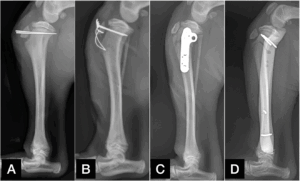

Commonly used implants in tibial growth plate fractures include orthopaedic pins (Figure 2A), wires (Figure 2B), and sometimes bone plate and screws (Figure 2C) or external fixator (Figure 2D).